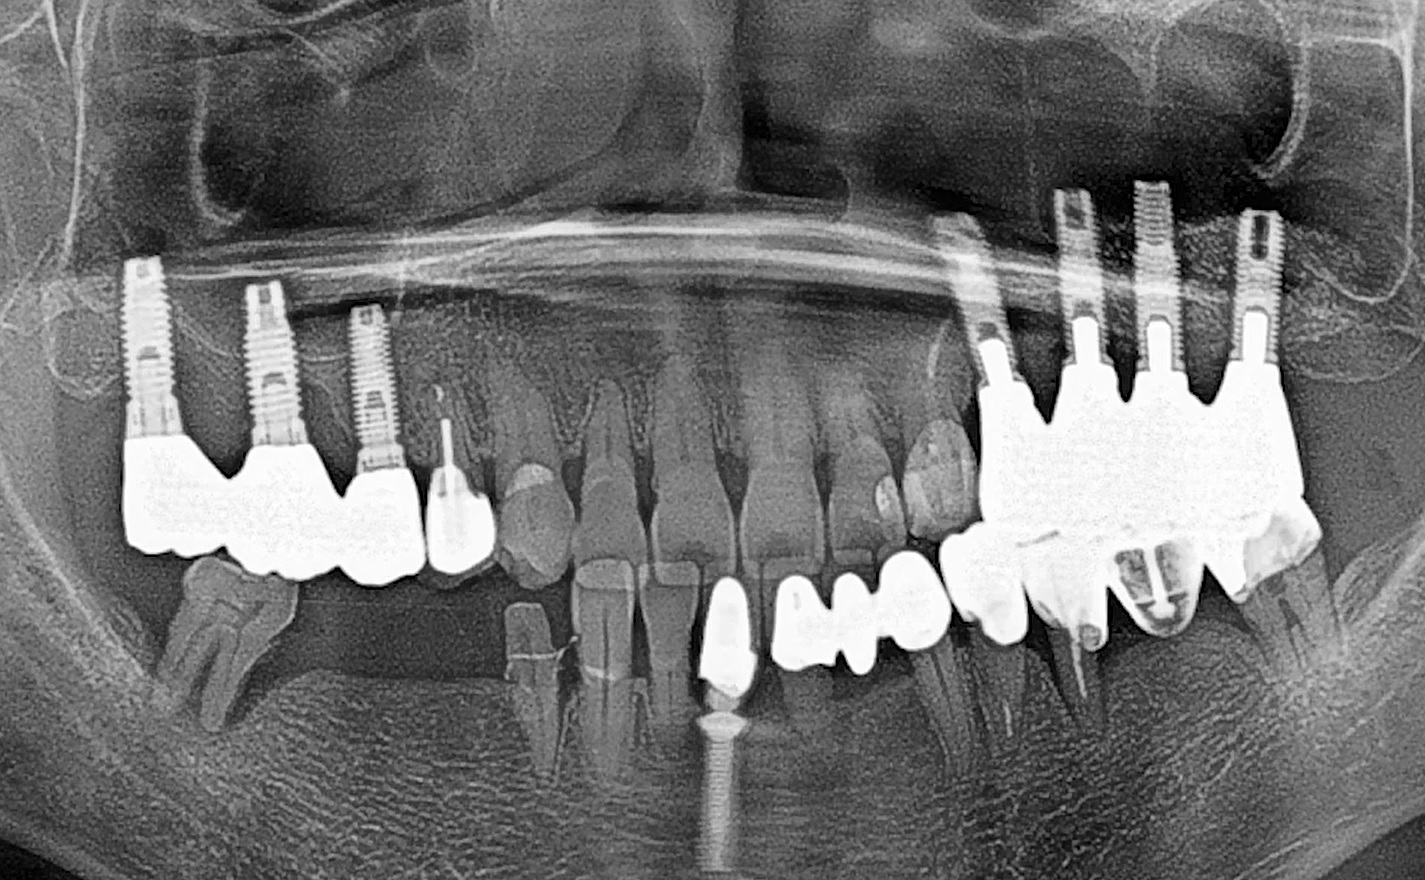

Dr Segin Chandran,Single replacement,Bone regeneration,Digital Guided Surgery,Maxillary Posterior,#25,Immediate Placement,Sinus Elevation,Guided surgery,AnyRidge,R2GATE Guide,R2GATE Surgical Kit(AnyRidge),MICA,Crestal elevation,Minimally invasive,Video